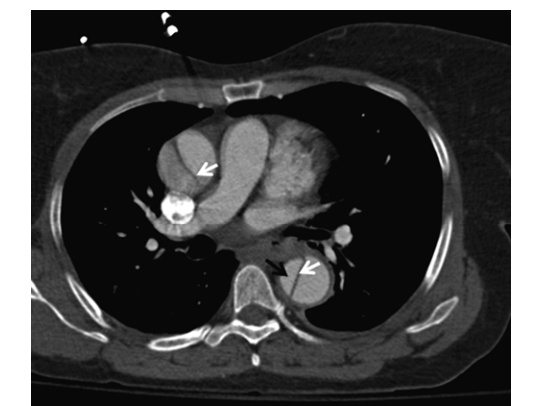

Aortic Dissection

Diagnosis